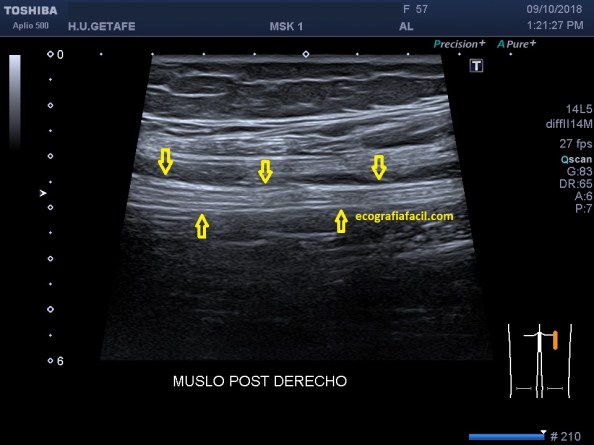

Me parece interesante que nos detengamos en un Nervio muy importante que circula por la parte posterior del muslo y que en muchas ocasiones se ve afectado e involucrado en dolor del miembro inferior, es el Nervio Ciático, que te voy a mostrar con ecografía para que lo puedas estudiar en pasos sencillos.

Es un nervio voluminoso que discurre por la profundidad del Muslo posterior, y es ecográficamente visible desde el Glúteo hasta su división cerca de la rodilla.

Ecográficamente es hiperecogénico, y se puede estudiar en todo el recorrido del Muslo.

La exploración es complicada por la ecogenicidad intrínseca del Nervio. La/el paciente estará decúbito prono y colocaremos nuestra sonda en la mitad del Fémur, allí encontraremos el Nervio Ciático, y partiendo de su visualización, donde es más fácil, iremos de proximal hasta distal recorriéndolo y estudiándolo tanto en transverso como en longitudinal.Así:

Visualización longitudinal del Nervio.

Como hemos observado el Nervio se objetiva Hiperecogénico, central y profundo en la musculatura del Muslo.